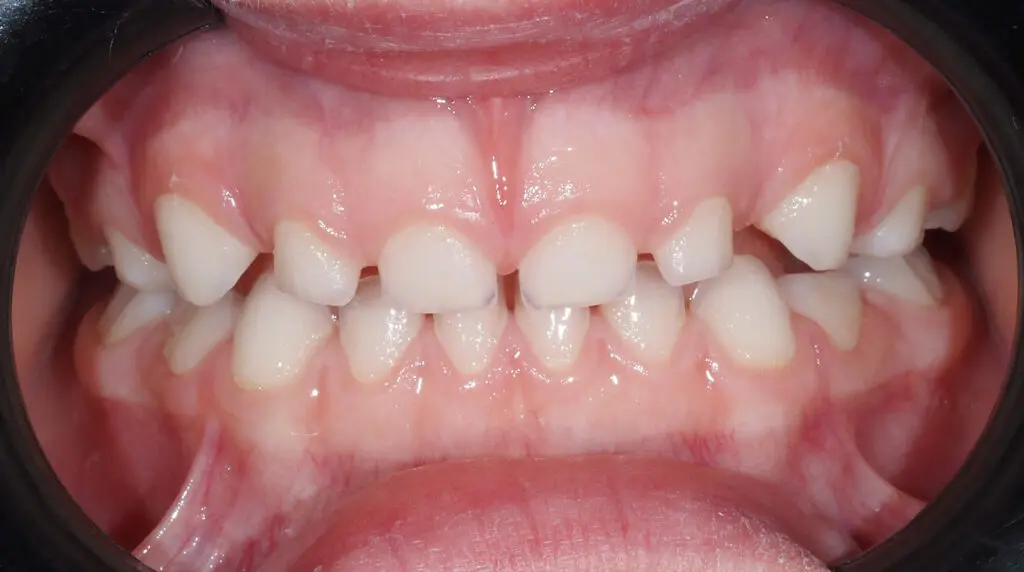

Tak wygląda powyższy pacjent po kilku miesiącach leczenia. Czy to dziecko już nie będzie potrzebować leczenia ortodontycznego? Tego nie wiemy, ale ma teraz szansę na prawidłowy dalszy wzrost, co ogranicza zakres potrzeb ewentualnego późniejszego leczenia. Tak powinien wygladać zgryz 5-latka bez interwencji ortodontycznej. Jeśli zgryz Twojego dziecka tak nie wygląda, zgłoś się do lekarza, żeby nie stracić tego cennego potencjału wzrostowego. Bo rośniemy tylko raz.

PO LECZENIU